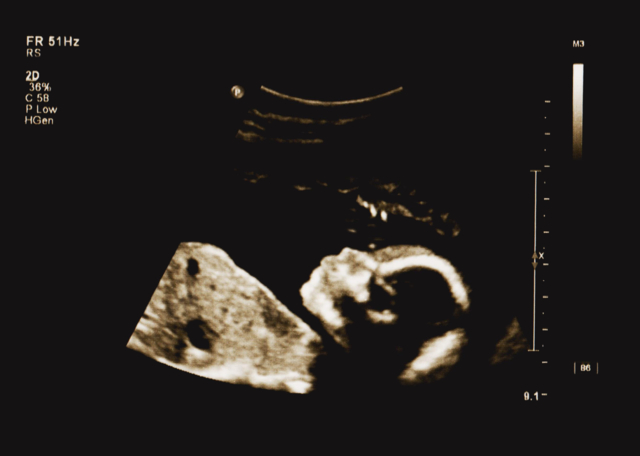

ภาวะมดลูกแตก คือภาวะที่ผนังมดลูกฉีกขาด มักพบได้บ่อยในคุณแม่มือใหม่ที่มีประวัติการรักษามดลูก รวมถึงพยายามคลอดทางช่องคลอดหลังจากเคยผ่าตัดคลอดมาก่อน เป็นภาวะแทรกซ้อนที่พบได้ไม่บ่อย แต่เป็นอันตรายต่อชีวิตทั้งมารดาและทารก และต้องได้รับการรักษาทันทีอย่างทันท่วงที

ภาวะมดลูกแตกถือเป็นภาวะฉุกเฉินทางการแพทย์ เนื่องจากอาจเป็นอันตรายถึงชีวิตทั้งต่อคุณแม่และทารกในครรภ์ ภาวะนี้จะทำให้เกิดรูโหว่ในมดลูกและช่องท้อง ซึ่งเป็นอันตรายอย่างยิ่ง และทำให้เสียเลือดมาก เมื่อมดลูกแตก ทารกในครรภ์จะไม่มีมดลูกคอยปกป้อง ทำให้หัวใจเต้นช้าลงและขาดออกซิเจน หากขาดออกซิเจน ทารกในครรภ์อาจเสี่ยงต่อภาวะสมองเสียหาย หรือขาดอากาศหายใจ แพทย์จะต้องดำเนินการอย่างรวดเร็ว เพื่อนำทารกออกมาและซ่อมแซมมดลูกของผู้เป็นแม่